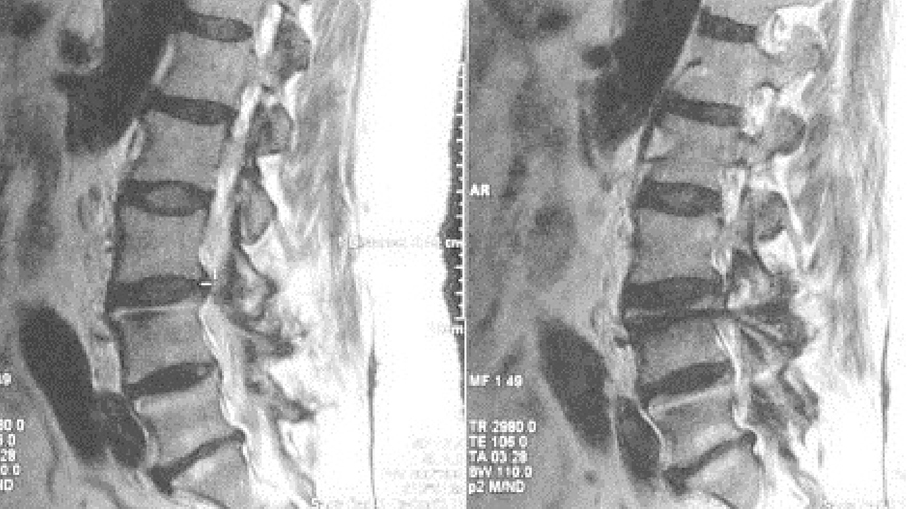

В связи с этим изменения Modic рассматриваются некоторыми специалистами как признак нестабильности, хотя существуют работы, опровергающие данный тезис [1]. Hayashi Т. et al., оценивая данные кинематических МРТ 450 пациентов, выявили значимую прямую корреляционную связь между изменениями Modic с дегенерацией МПД по Pfirrmann, а также с трансляционно-ангуляционными изменениями в ПДС (рисунок 3) [19]. Они определили, что наибольшая мобильность ПДС прослеживается при изменениях I типа, а трансляция – при II типе Modic. Не исключено, что в случае изменений Modic имеет место быть так называемая клиническая, или функциональная, нестабильность по теориям Panjabi М.М. и Beazell J.

Рисунок 3. МРТ ПОП. В ПДС L3-4 по данным функциональной спондилографии имеется нестабильность. По МРТ сохранена высота МПД L3-4 и отмечается II ст. дегенерации по Pfirrmann.